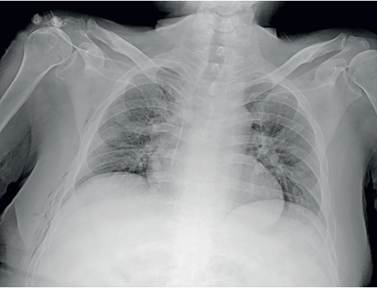

Se realizó PET-CT que reportó neumotórax derecho como hallazgo incidental, confirmado por radiografía de tórax (Figura 1), por lo que se indicó toracostomía cerrada. Durante el procedimiento se evidenció salida de aire a presión y producción de 150 cc de líquido de aspecto seroso; se colocó un tubo de tórax 32 Fr, que se conectó a sistema Pleur-Evac® y succión a -10 cm de agua.

En la radiografía de tórax de control, aproximadamente una hora posterior al procedimiento, se documentaron áreas de consolidación multilobar unilateral derechas y neumotórax residual (Figura 2), por lo que se continuó con succión a -30 cm de agua y se solicitó tomografía computarizada (TC) de tórax, confirmando los hallazgos (Figura 3). Teniendo en cuenta el procedimiento realizado y secuencia de imágenes, se consideró que el paciente cursaba con edema pulmonar por reexpansión. Se inició terapia respiratoria e incentivo respiratorio, y se logró el retiro del tubo de tórax cuatro días después, sin complicaciones. En el seguimiento radiológico al sexto día se apreciaba resolución de los hallazgos imagenológicos (Figura 4).

Aunque la clínica de deterioro respiratorio puede sugerir el diagnóstico, la secuencia de imágenes es la base fundamental. Como primera imagen, la radiografía de tórax posterior al procedimiento usualmente no revela alteraciones parenquimatosas; 2 a 4 horas después se suele evidenciar en más del 90 % de los pacientes un patrón de ocupación alveolar unilateral, que resuelve entre 5 y 7 días, sin secuelas radiológicas. En la TC se demuestran opacidades en vidrio esmerilado, engrosamiento septal, focos de consolidación y áreas de atelectasia usualmente ipsilateral al procedimiento, aunque puede ser bilateral 1.